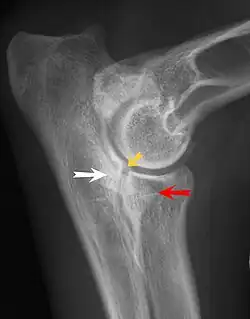

Most primary lesions are related to osteochondrosis, a disease of the joint cartilage, and osteochondritis dissecans (OCD), the separation of a flap of cartilage on the joint surface. Other common causes of elbow dysplasia include an ununited anconeal process (UAP) and fragmented or ununited medial coronoid process (FCP or FMCP).[1]

The most common cause is osteochondrosis, which is a disease of the joint cartilage, and osteochondritis dissecans (OCD or OD), the separation of a flap of cartilage from the joint surface[1] as a result of avascular necrosis, which in turn arises from failed blood flow in the subchondral bone.[3]

In OCD, the normal change of cartilage to bone in the development of the joint fails or is delayed. The cartilage continues to grow and may split or become necrotic. The cause is uncertain, but possibly includes genetics, trauma, and nutrition (including excessive calcium and decreased vitamin C intake).[4] OCD lesions found in the elbow at the medial epicondyle of the humerus are caused by disturbed endochondral fusion of the epiphysis of the medial epicondyle with the distal end of the humerus, which may in turn be caused by avulsion of the epiphysis.[5] Specific conditions related to OCD include fragmentation of the medial coronoid process of the ulna (FMCP) and an ununited anconeal process of the ulna (UAP). All types of OCD of the elbow are most typically found in large breed dogs, with symptoms starting between the ages of 4 and 8 months.[4] Males are affected twice as often as females. The disease often affects both elbows (30 to 70 percent of the time), and symptoms include intermittent lameness, joint swelling, and external rotation and abduction of the paw.[6] Osteoarthritis will develop later in most cases.

UAP is caused by a separation from the ulna of the ossification center of the anconeal process.[7] FMCP is caused by a failure of the coronoid process to unite with the ulna.

Diagnosis is through x-rays, arthroscopy or CT (computed tomography). In cases with significant lameness, surgery is the best option, especially with UAP. However, conservative treatment is often enough for cases of FMCP and OCD of the medial humeral epicondyle. The dogs are exercised regularly and given pain medication, and between the ages of 12 and 18 months the lameness will often improve or disappear.[4] Control of body weight is important in all cases of elbow dysplasia, and prevention of quick growth spurts in puppies may help to prevent the disease.